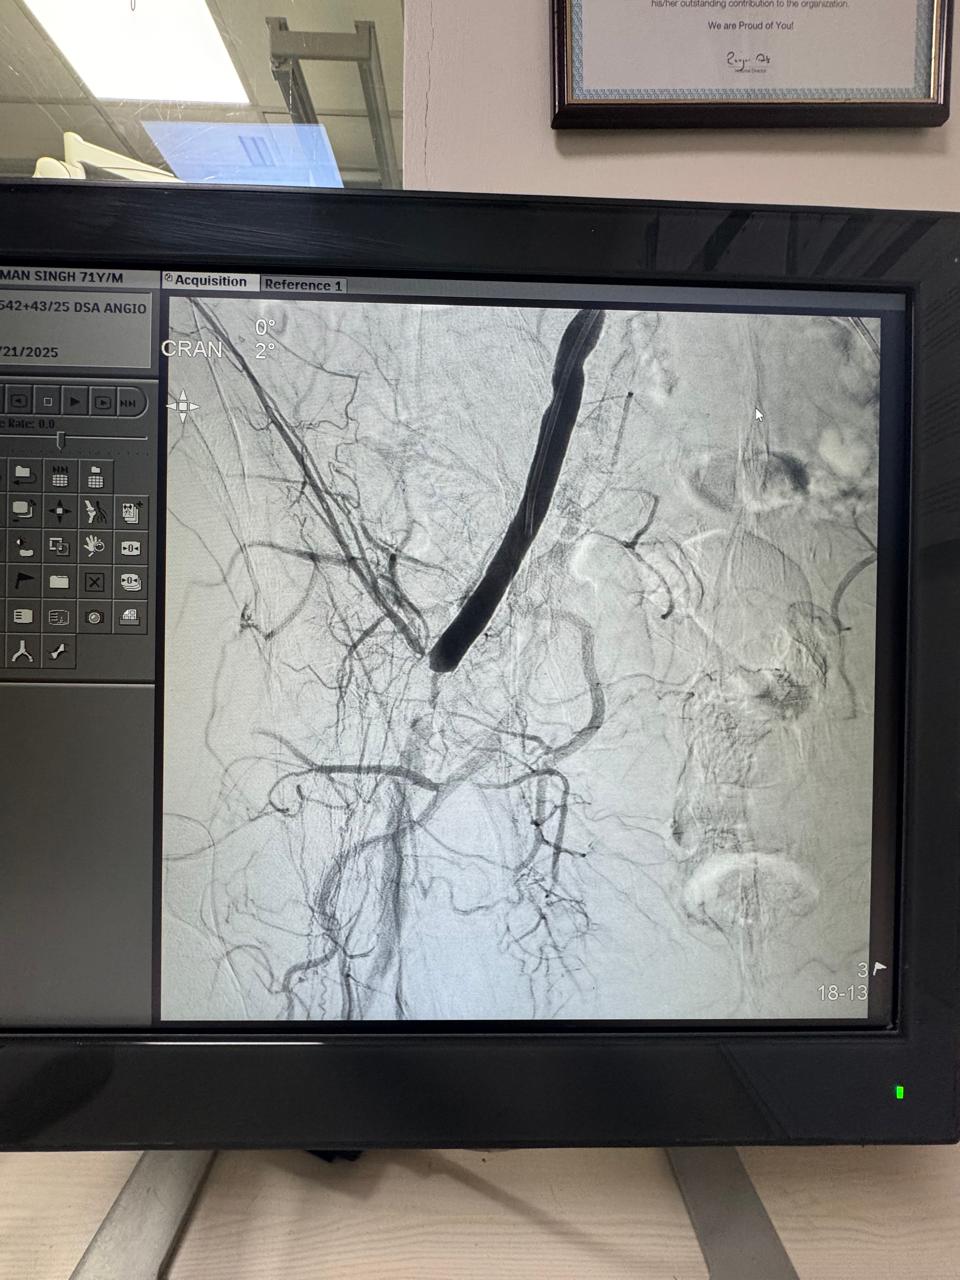

Right Renal Artery Stenting- Ostial crtiacal stenosis and hypentensive patient, blood pressure not controlled with three antihypertensive drugs.